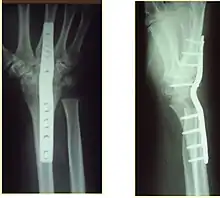

Surgery is generally indicated for displaced or unstable fractures.[18] The techniques of surgical management include open reduction internal fixation (ORIF), external fixation, percutaneous pinning, or some combination of the above. The choice of operative treatment is often determined by the type of fracture, which can be categorized broadly into three groups: partial articular fractures, displaced articular fractures, and metaphyseal unstable extra- or minimal articular fractures.[5]

Significant advances have been made in ORIF treatments. Two newer treatments are fragment-specific fixation and fixed-angle volar plating. These attempt fixation rigid enough to allow almost immediate mobility, in an effort to minimize stiffness and improve ultimate function; no improved final outcome from early mobilization (prior to 6 weeks after surgical fixation) has been shown. Although restoration of radiocarpal alignment is thought to be of obvious importance, the exact amount of angulation, shortening, intra-articular gap/step which impact final function are not exactly known. The alignment of the DRUJ is also important, as this can be a source of a pain and loss of rotation after final healing and maximum recovery.

Surgical options have been shown to be successful in patients with unstable extra-articular or minimal articular distal radius fractures. These options include percutaneous pinning, external fixation, and ORIF using plating. Patients with low functional demand of their wrists can be treated successfully with nonsurgical management; however, in more active and fit patients with fractures that are reducible by closed means, nonbridging external fixation is preferred, as it has less serious complications when compared to other surgical options.[5] The most common complication associated with nonbridging external fixation is pin tract infection, which can be managed with antibiotics and frequent dressing changes, and rarely results in reoperation.[5] The external fixator is placed for 5 to 6 weeks and can be removed in an outpatient setting.[5]

If the fractures are unlikely to be reduced by closed means, open reduction with internal plate fixation is preferred.[5] Although major complications (i.e. tendon injury, fracture collapse, or malunion) result in higher reoperation rates (36.5%) compared to external fixation (6%), ORIF is preferred, as this provides better stability and restoration of the volar tilt.[5][23] Following the operation, a removable splint is placed for 2 weeks, during which time patients should mobilize the wrist as tolerated.[5]